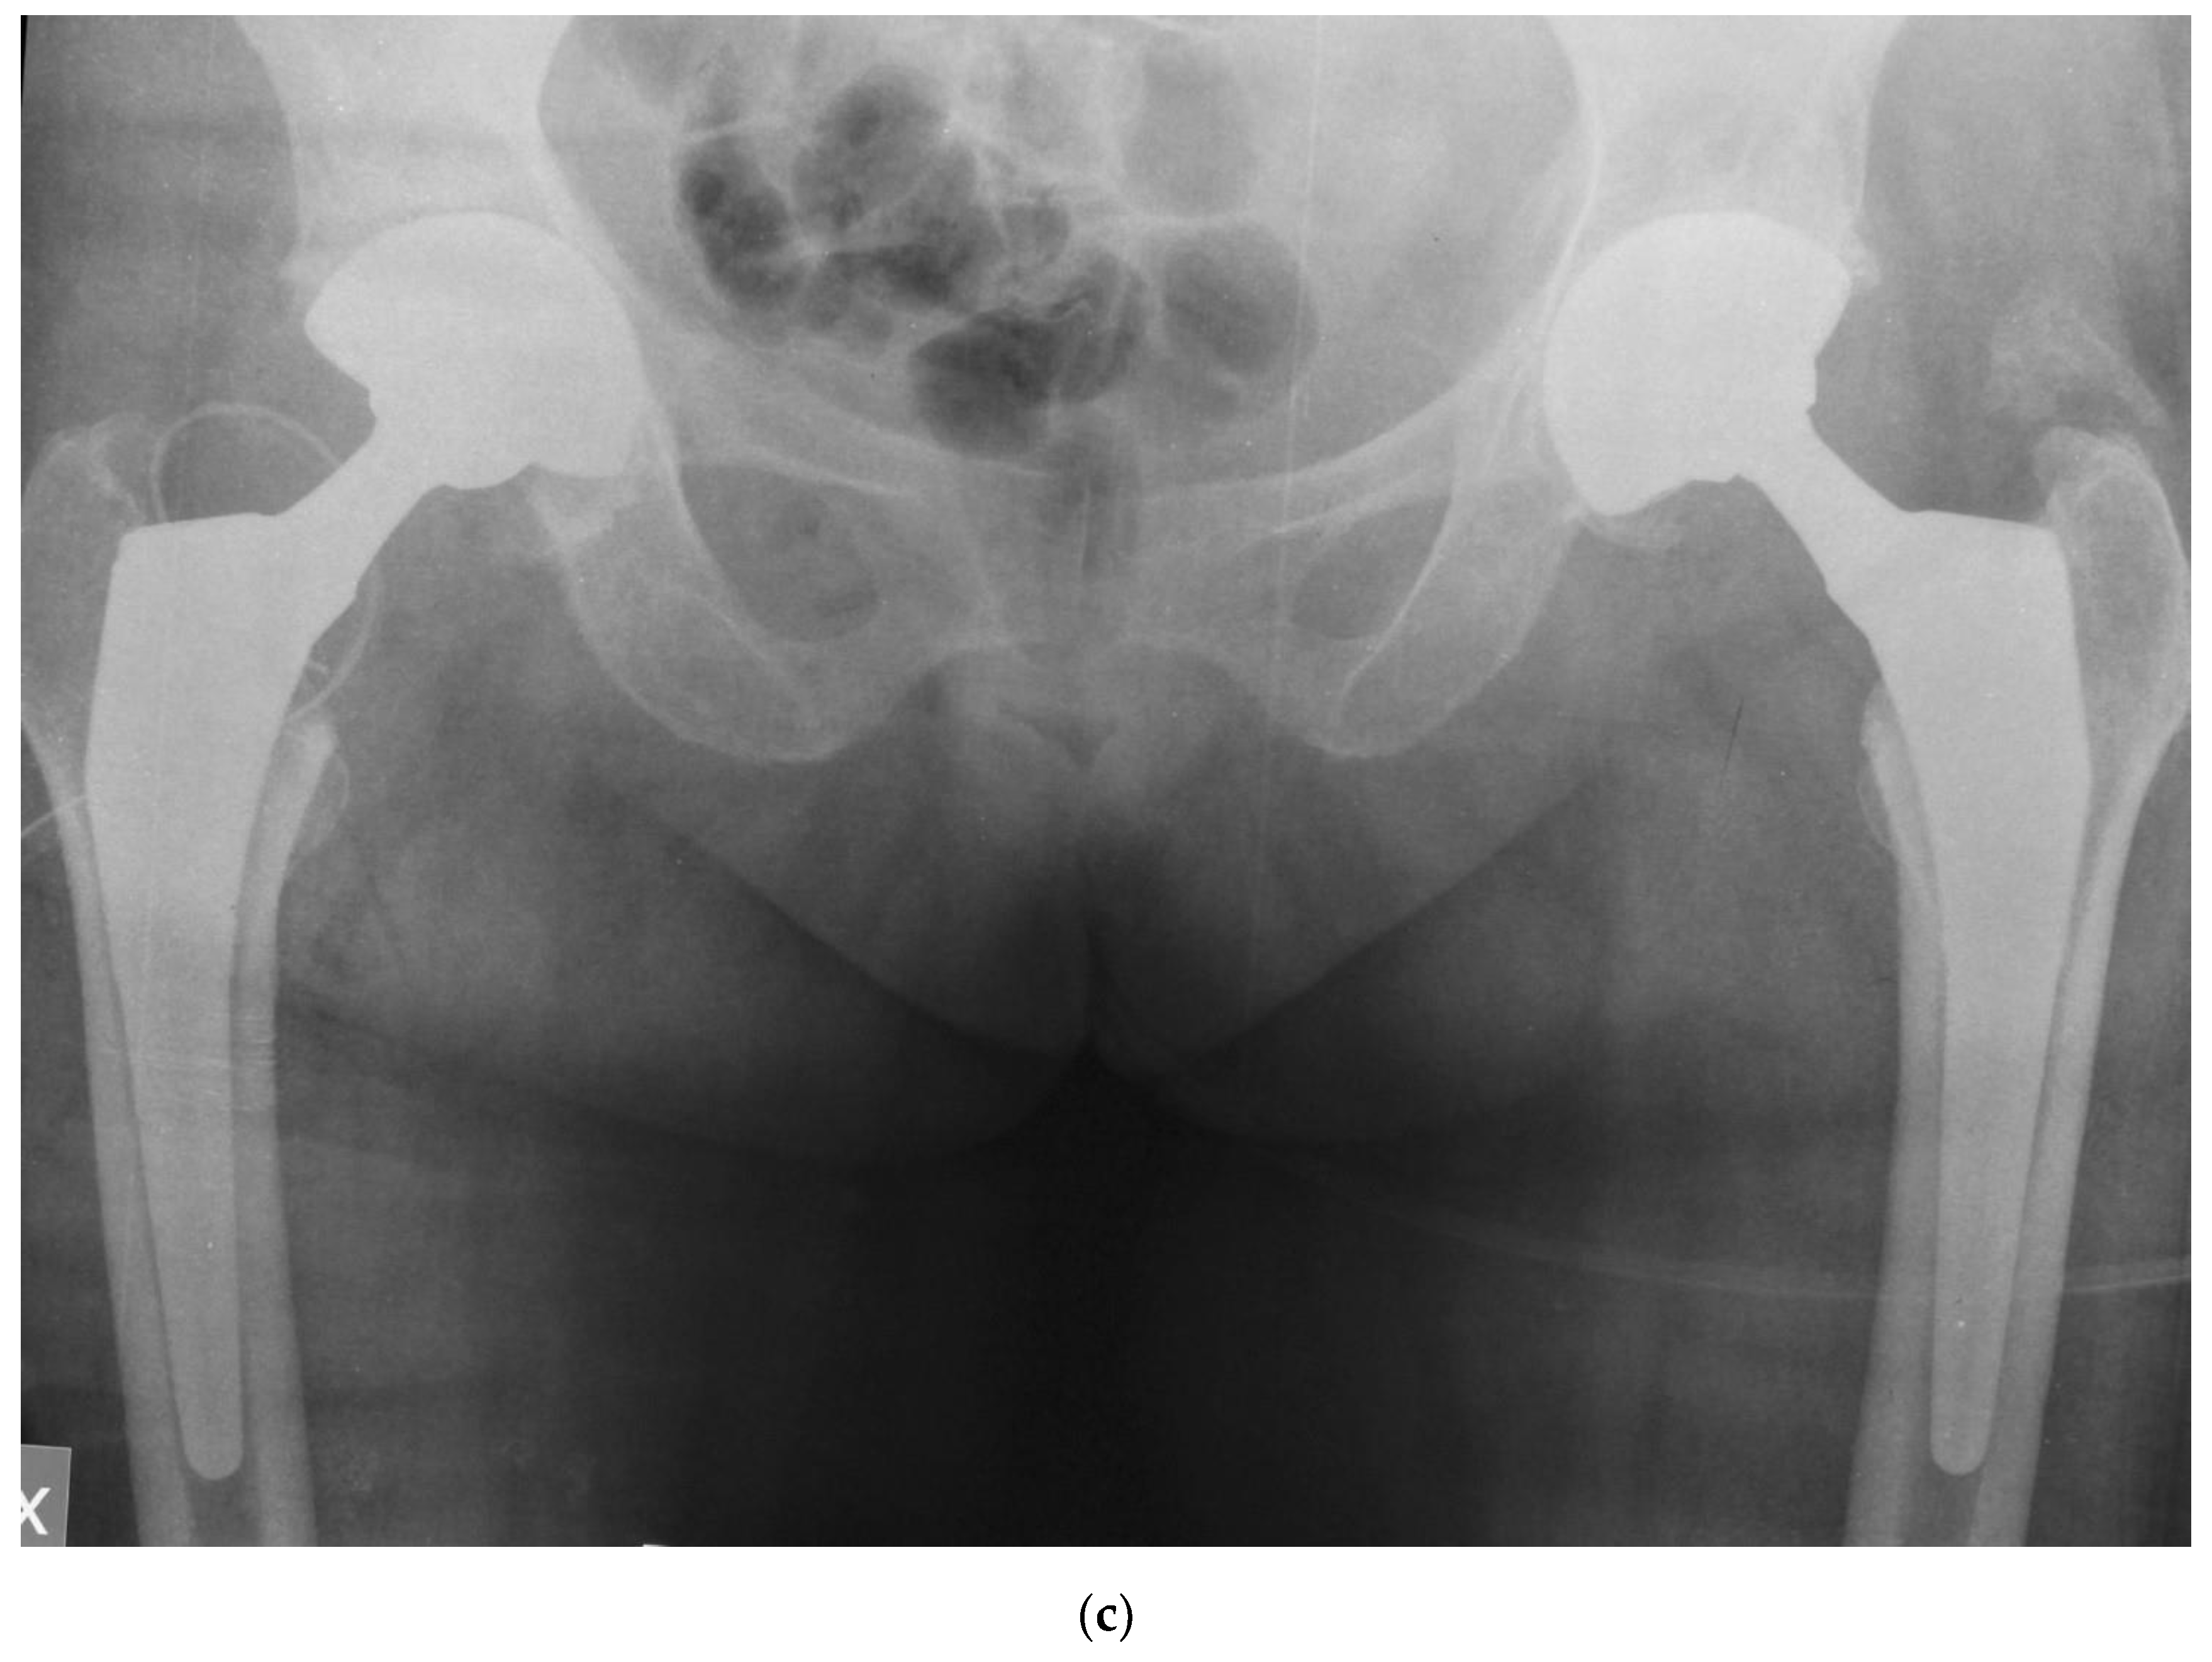

Figure 3 shows the case of a 68 years old female, who was referred to our unit due to persistent low back pain for vertebral steno-instability and consequent sagittal imbalance to undergo spinal lumbo-sacral fusion; clinical and radiological examinations revealed a concomitant severe osteoarthritis in both her hips that was treated with bilateral THA with the G7 modular cementless DM cup. After surgical treatment in the hips, low back pain improved dramatically, and the patient did not need any surgery in her spine.

Figure 3. steno-instability and consequent sagittal imbalance oh the spine (a); severe bilateral hip osteoarthritis (b); staged bilateral total hip replacements using DM modular cups and cementless stems (c).